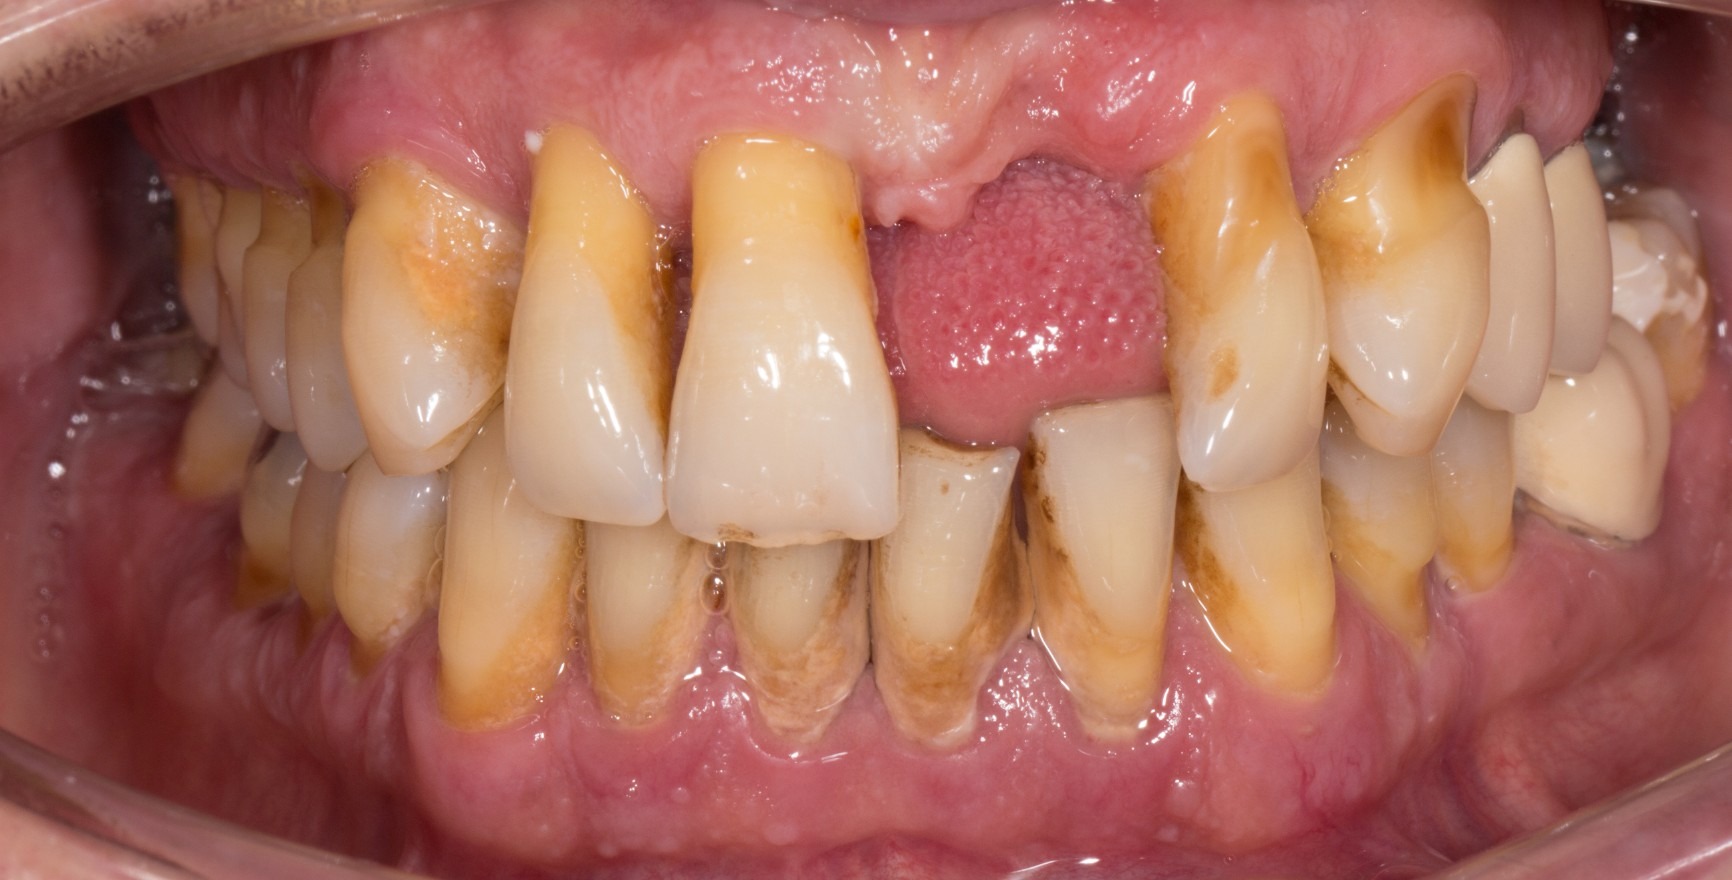

A state of clinical periodontal health in the intact periodontium is distinguished from that in a reduced periodontium already affected by clinical loss of attachment. This loss of attachment can occur:

as result of inflammation during the course of periodontitis. Clinical periodontal health then describes a stable condition after successful completion of periodontal treatment.

as the result of recession

The clinical criterion is always the absence of bleeding on careful probing (bleeding on probing = BoP). A distinction is made between a site/tooth-specific diagnosis with a negative BoP finding at the corresponding measurement site, and diagnosis on the level of the tooth or patient, for which a threshold value of a BoP ≤ 10% still meets the criteria of clinical periodontal health. Pocket probing depths must be no more than 3 mm. In a reduced periodontium after periodontal treatment, a threshold value of 4 mm is still regarded as a stable status (Matuliene et al., 2008).